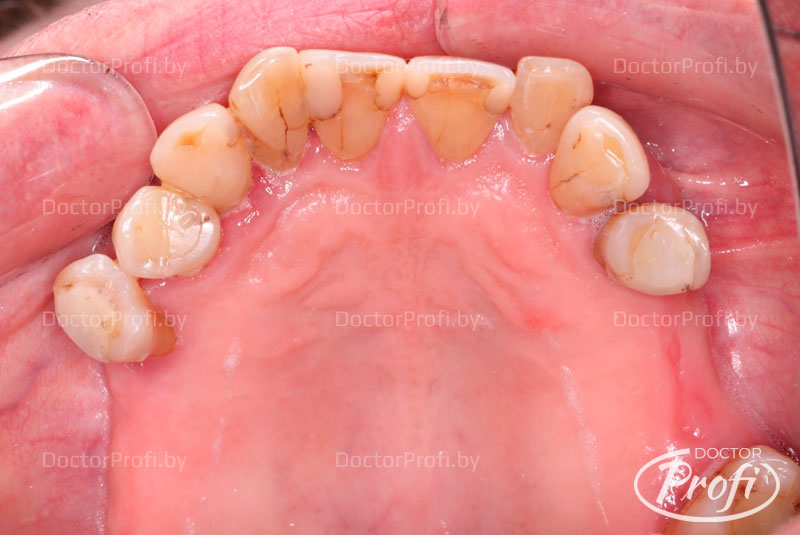

К нам обратился пациент 70 лет с жалобами на подвижность зубов верхней нижней челюсти, а также на периодически возникающие боли в этих зубах. Исходная ситуация была следующей. В полость рта определялись зубы, которые были подвижности первой и второй степени. Мосты были несостоятельны, то есть мостовидные протезы были изготовлены более 10 лет назад. Они были расколоты и также были подвижные опорные зубы.

Изготовлен и установлен металлокерамический протез на верхнюю челюсть и металлокомпозитный протез на нижнюю челюсть.